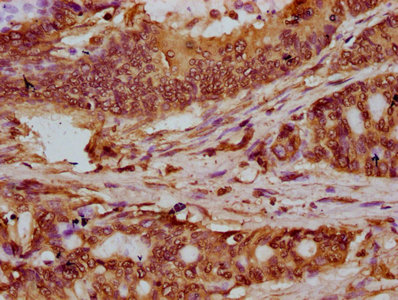

IHC image of CSB-PA010403OA120nbhbHU diluted at 1:20 and staining in paraffin-embedded human colon cancer performed on a Leica BondTM system. After dewaxing and hydration, antigen retrieval was mediated by high pressure in a citrate buffer (pH 6.0). Section was blocked with 10% normal goat serum 30min at RT. Then primary antibody (1% BSA) was incubated at 4°C overnight. The primary is detected by a biotinylated secondary antibody and visualized using an HRP conjugated SP system.